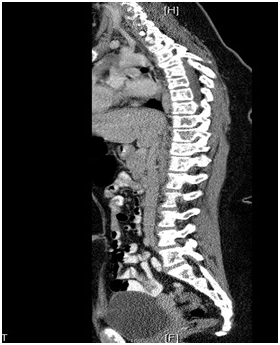

A 12-year-old Saudi girl with a known case of vitamin D deficiency and acute β-cell lymphoblastic leukemia presented to the emergency department complaining of fever, generalized bone pain for two months, and sternal prominence for one month, with no history of weight loss, masses, or swellings. On examination, she looked pale with generalized bone ache. There was a prominent sternal projection, which was not tender. No obvious lymphadenopathy or hepato-splenomegaly was detected. Further testing showed the following values: CBC: 9.59; absolute neutrophil count: 6.42; hemoglobin: 7.9; platelets: 295; Uric acid: 503 µmol/L; LDH: 754 µmol/L; Creatinine: 57 mmol/L; calcium: 2.5 mmol/L; alkaline phosphatase: 161 units/L; phosphate: 1.31 mmol/L; and potassium: 3.8 mmol/L. Her T-cell marker and myeloid markers were negative. A CT scan of the chest and abdomen displayed compression fractures extending from T1 to T6, with diffused mixed lytic and sclerotic osseous changes all over the skeleton, as shown in Figure 4. Moreover, there were multiple low attenuation lesions in the mildly enlarged kidneys. An MRI of the spine showed diffused abnormal heterogeneous appearance of the bone marrow over the entire spine and the sacrum (Figure 5), but no clear cord compression was seen. Bone scintigraphy with 99mTc-methylene diphosphonate showed diffused increase in tracer uptake in the skeleton. Patchy, geographic like elevated uptake was seen in the skull (Figure 6). The patient was on Tazocin, amikacin and voriconazole, and vitamin D 50,000 IU weekly.

Figure 4 A CT scan with compression fractures extending from T1 to T6, with diffused mixed lytic and sclerotic osseous changes all over the skeleton.

Figure 5 An MRI showing diffused abnormal heterogeneous appearance of the bone marrow over the entire spine and the sacrum.

In case 2, the images showed compression fractures extending from T1 to T6, with diffused mixed lytic and sclerotic osseous changes all over the skeleton. Moreover, an MRI showed the diffused abnormal heterogeneous appearance of the bone marrow over the entire spine and the sacrum. These findings conform to what is documented in the literature and the orthopedic doctors who find such signs should suspect leukemia, which can still be diagnosed at an early stage for a good prognosis and a chance to save lives.